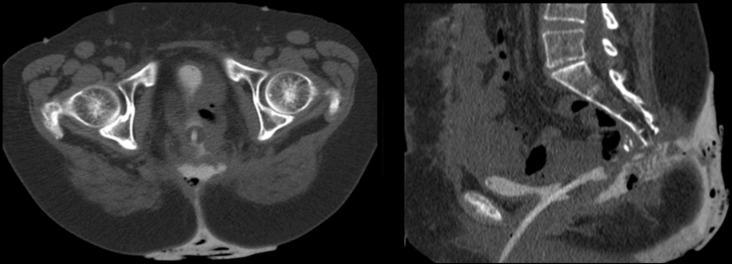

Urinary bladder fistula formation is a complication of significant morbidity and mortality following pelvic surgery or radiotherapy. Surgical treatment is the definitive management, but it may be contraindicated in patients with significant comorbidities. The alternative approach is to divert urine away from the fistula with stents and catheters, and allow time for healing. The case illustrated herein describes the use of alcohol to accelerate the fibrotic healing of a urinary bladder fistula, based on the premise that sclerosing agents have been effective in the treatment of pancreatic fistulas and renal cysts. A Foley catheter is inserted through the external fistula orifice and passed along the fistula tract into the urinary bladder. The Foley catheter balloon is inflated and pulled back to occlude the fistula. Following this, a vascular sheath is placed alongside the catheter and ethanol is injected into the tract. The alcohol is left to dwell in the fistula for a few minutes, after which time the catheter and sheath are removed. The sclerosant effect of the ethanol aims to induce fibrosis, and therefore occlusion, of the fistula.

膀胱瘘形成是盆腔手术或放疗后具有较高发病率和死亡率的一种并发症。手术治疗是确定性的治疗方法,但对于有严重合并症的患者可能是禁忌的。另一种方法是使用支架和导管将尿液从瘘口引流开,留出愈合时间。本文所述病例描述了基于硬化剂在治疗胰瘘和肾囊肿方面有效的前提,使用酒精加速膀胱瘘的纤维化愈合。将一根Foley导尿管通过外瘘口插入,并沿瘘管进入膀胱。将Foley导尿管的球囊充气并拉回以阻塞瘘管。在此之后,将一个血管鞘放置在导管旁边,并将乙醇注入瘘管。让酒精在瘘管中停留几分钟,之后取出导管和鞘。乙醇的硬化作用旨在诱导瘘管纤维化,从而实现阻塞。